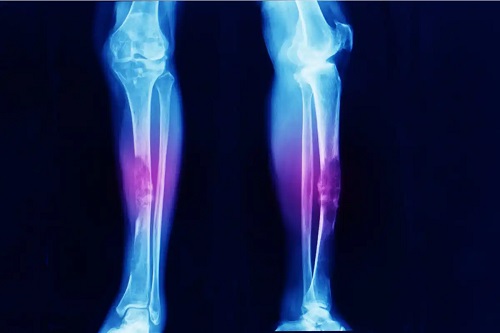

- Fracturi sau traumatisme care nu pot fi observate la radiografie